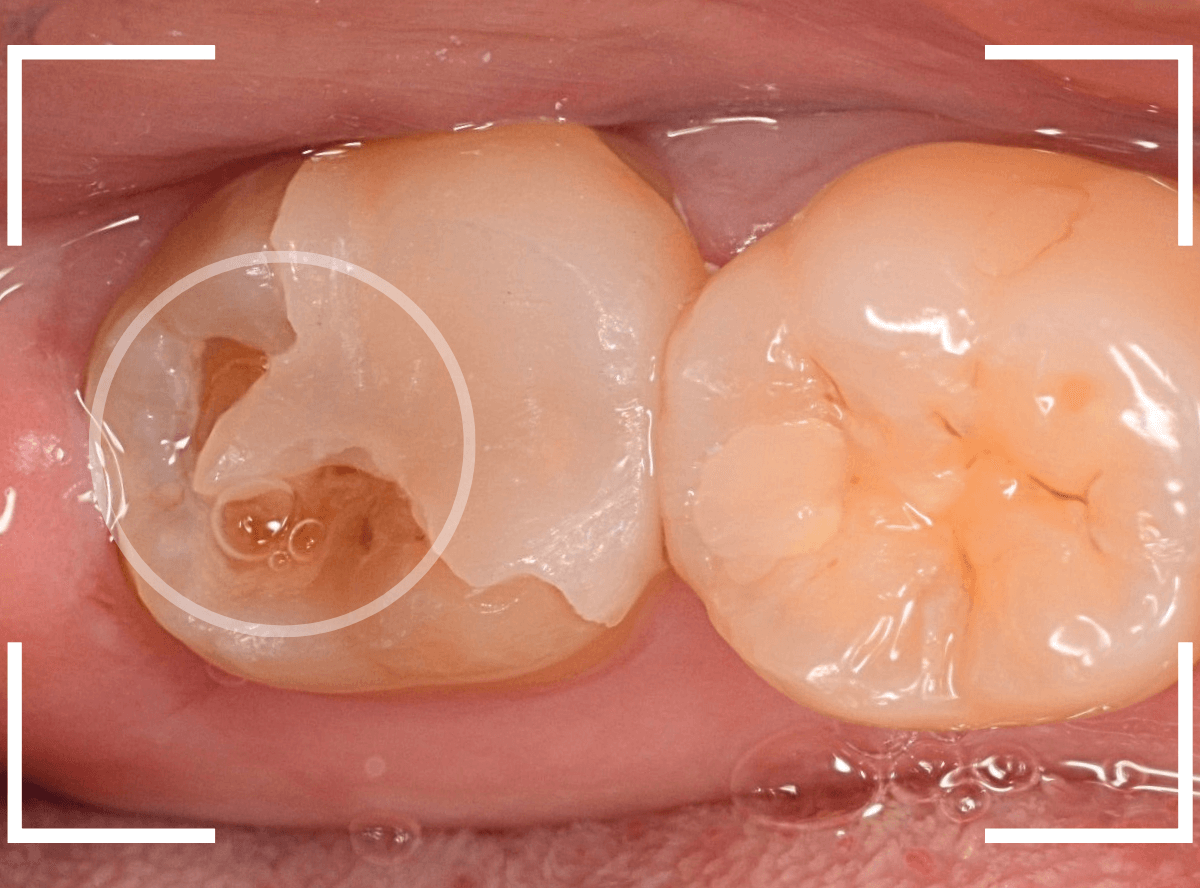

Case.28 虫歯治療後、半年以上来院されなかった患者さん

虫歯を治療して、セメントで歯を削った部分を封鎖した後、再修復を検討中で、半年以上来院されなかった患者さんです。

虫歯を治療して、セメントで封鎖した状態というのは、家でいえば、しっかりした屋根がない状態です。

今回は、セメントの一部がはがれる程度で済んでいましたが、虫歯が再発し、再治療、最終修復物の変更の可能性も出てきます。

皆さんも治療は中断せずに最後まで通院するようにしてくださいね。

治療再開後、セラミックの最終修復を希望されましたので、歯をトリミングし、型取りします。